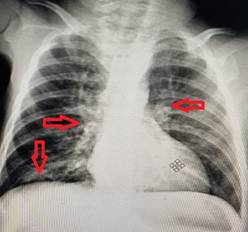

La conducta diagnóstica incluyó hemograma completo con eritrosedimentación, la cual mostró una hemoglobina en 67 g/L, traducida en una anemia severa. El estudio de lámina periférica reveló anisocromía, anisocitosis, microcitosis y leucocitos normales con ligera linfocitosis. Además, se realizó radiografía de tórax en vista posteroanterior donde se observaron engrosamientos perihiliares bilaterales y aumento de la radiopacidad en la región paracardíaca derecha. (Ver figura 1).

Fig. 1. Radiografía de Tórax vista PA